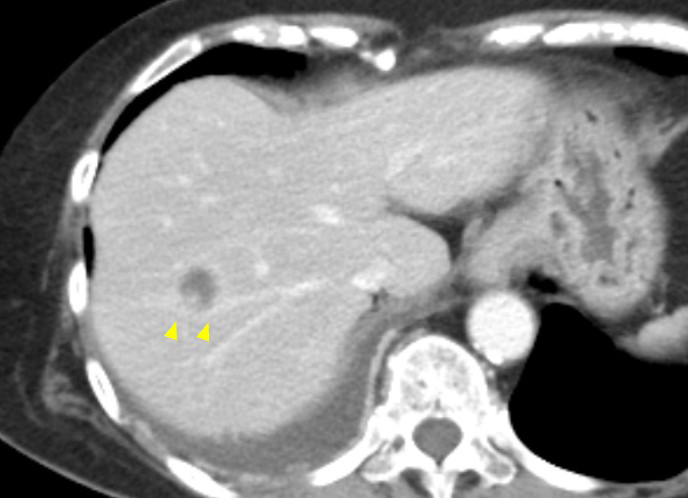

退院後経過:本人や家族との相談結果,術後補助化学療法は施行せず経過観察となった.術後2か月目に食思不振を訴え,CTで肝転移および胸膜播種巣を認めた(Fig. 5).術後4か月目には新たに腹膜播種の所見もみられ,術後5か月目に永眠された.

Abdominal CT showed liver metastasis.